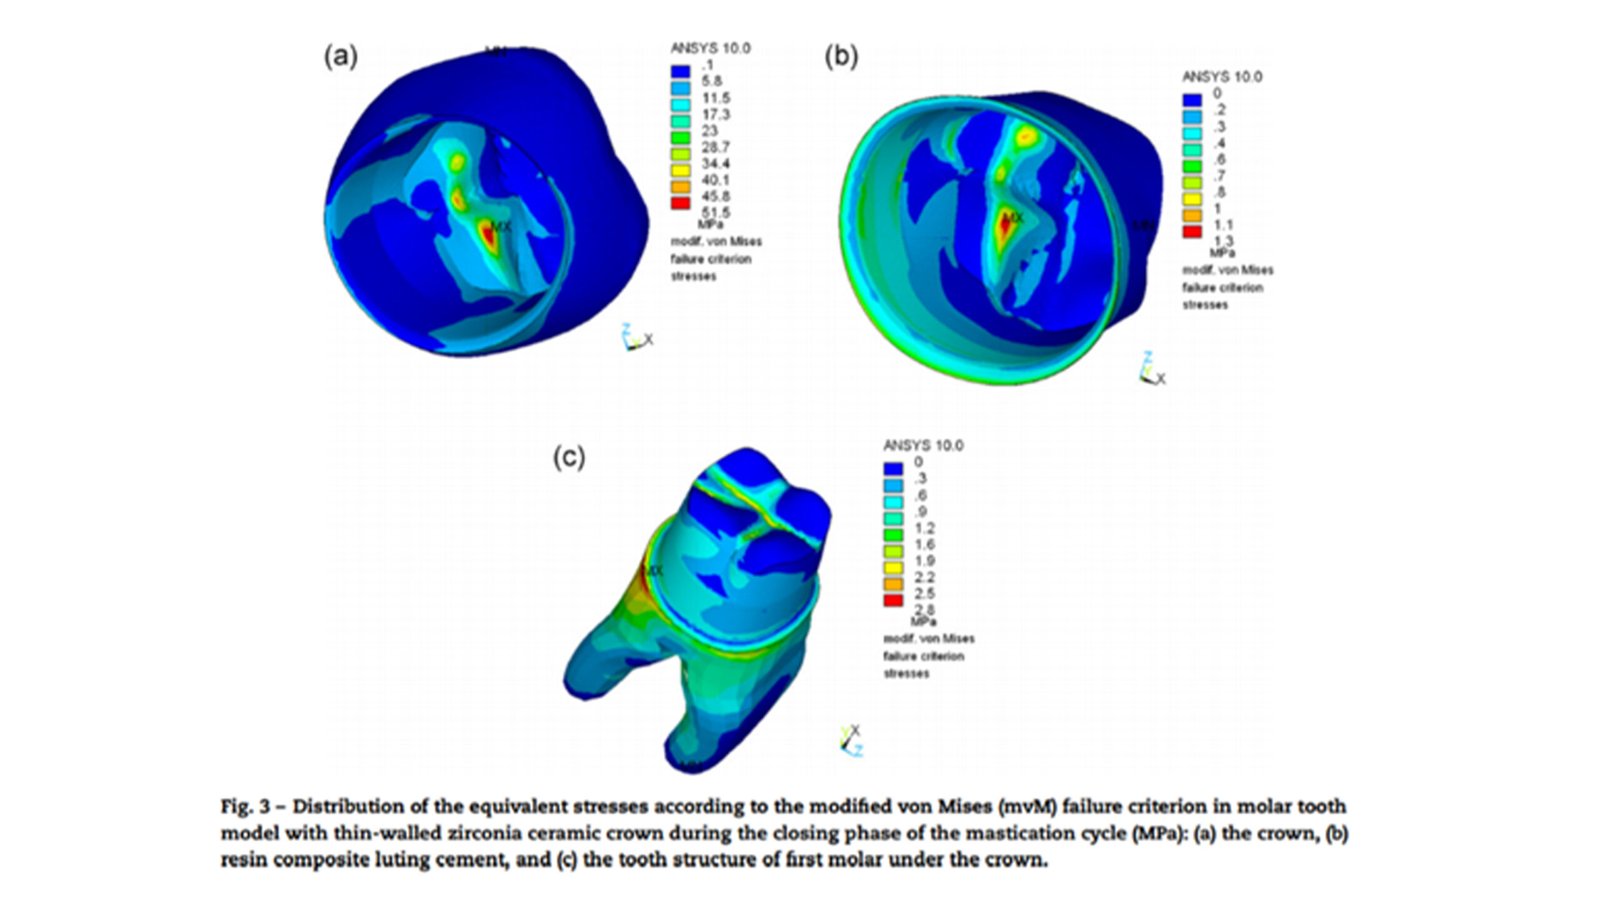

The Endodontic FEA section evaluates the biomechanical performance of root canal–treated teeth, endodontic tools, and reinforcement strategies. Through precise material characterization and micro-CT–based superimposition, we assess fracture risk, stress pathways, and instrument fatigue under various clinical scenarios. These simulations guide the selection of safer instrumentation techniques and restorative strategies. Our goal is to enhance predictability and reduce procedural complications.